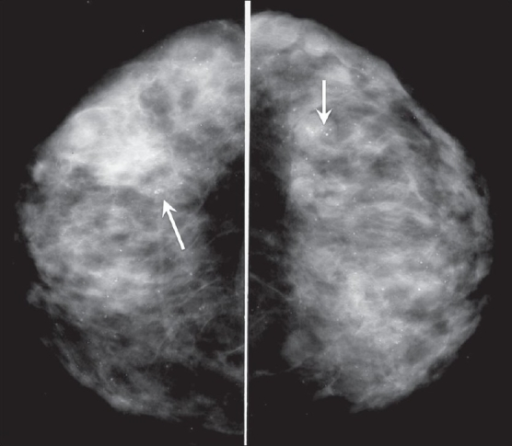

Radial Scar

Radial scars (complex sclerosing lesions) are hardened areas of breast tissue surrounded by abnormal ducts and tissue structures. Most radial scars are found on mammograms. As they resemble cancer, they require core biopsy for testing. Surgical excision is often recommended to confirm the surrounding tissue is normal. A referral to a breast surgeon is required for further investigation.

Pictorial essay: Breast USG by G. Shah and B. Jankharia is licensed under CC BY 2.0